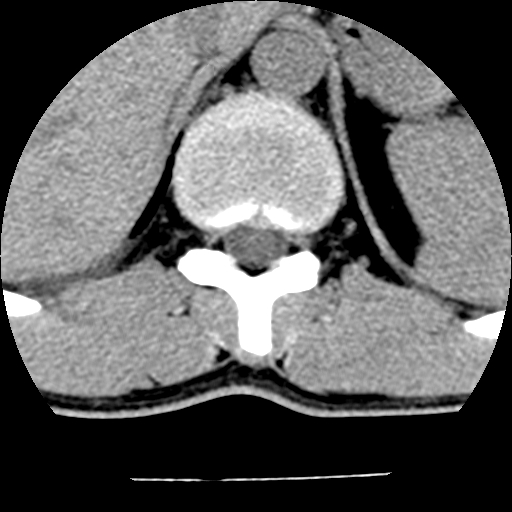

男,31岁,从6米高处坠落伤两天,腰背部疼痛,临床要求ct扫描胸10-腰1。请大家帮忙看看骨质有问题吗?

t12、l1锥体前缘轻度楔形变,平扫示椎体前缘骨小梁欠规整,第9幅图示椎体前缘骨质不连续,结合外伤史考虑椎体轻度压缩骨折。

楼主扫描层厚可能较大,每个椎体只有三个层面.

从所示层面分析,无明确骨折征象,象类似病人我个人会建议mri除外骨挫伤.

从上查骨窗第九片椎体前缘皮质显示断裂.压缩骨折?